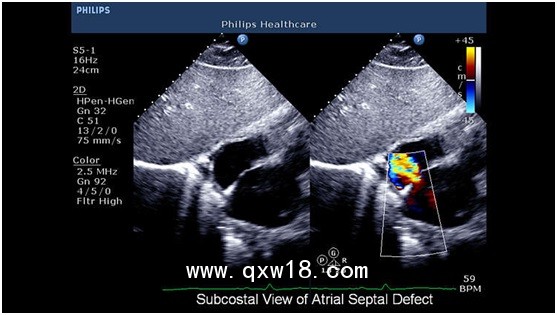

飛利浦彩超CX50產(chǎn)品說明:

CX50可移動高集成超聲診斷系統(tǒng) 引領(lǐng)超聲新浪潮,CX50是市場上第一款高集成的移動超聲診斷系統(tǒng),它將大型高檔彩超iE33/iU22的優(yōu)異平臺與便攜性能集于一身,為患者提供更高品質(zhì)的醫(yī)療服務(wù),更靈活的移動選擇,提高醫(yī)師的工作效率。

2? 心臟超聲